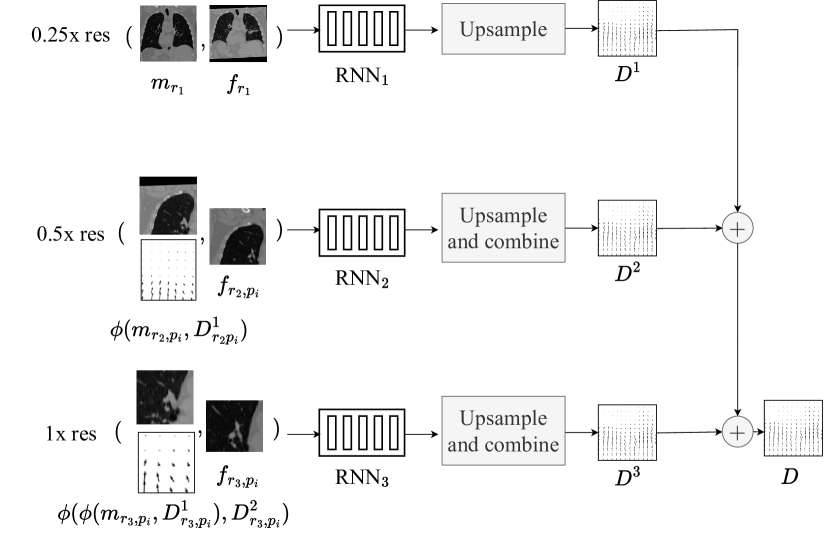

We adopt a course to fine approach to image registration. For each resolution, , a new RNN is trained using inputs from the previous resolution. The weights from previous resolutions are frozen at finer resolutions. At fine resolutions computing the cost volume for the whole volumes becomes prohibitively expensive; as such, our approach divides the input images into uniform, non-overlapping windows or patches. The size of the patches at each resolution is parameterized by the ‘patch factor’, . The size of the patches at resolution is computed as where is the size of the full image at resolution. At higher resolutions, the flow field is used to warp the initial moving image (or patch) using flow fields computed at lower resolutions. Furthermore, the final hidden state is cached at lower resolutions and added to the initial hidden state at higher resolutions, increasing the non-linearity of the network and providing additional context to the network.